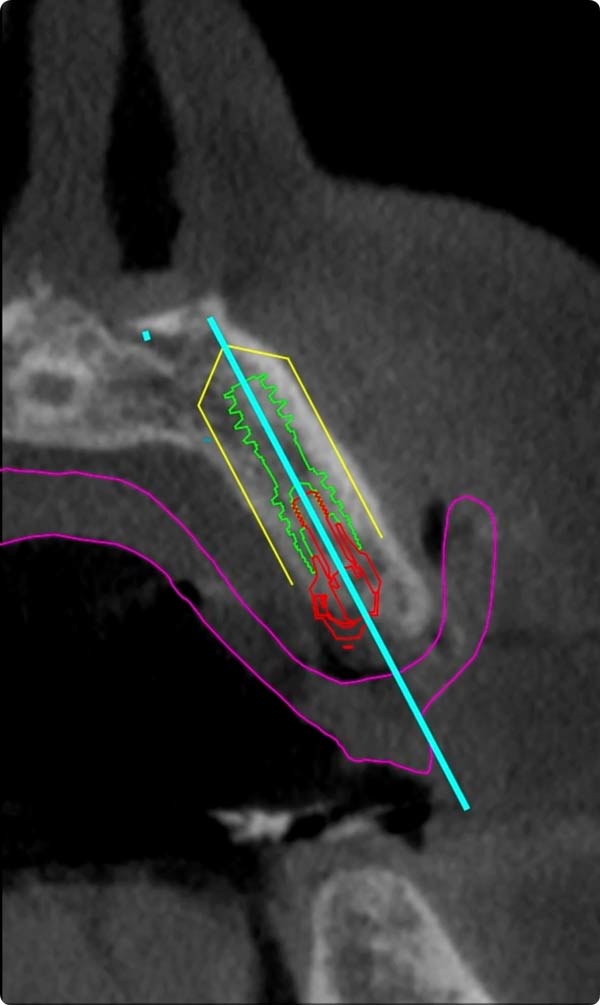

診査・診断